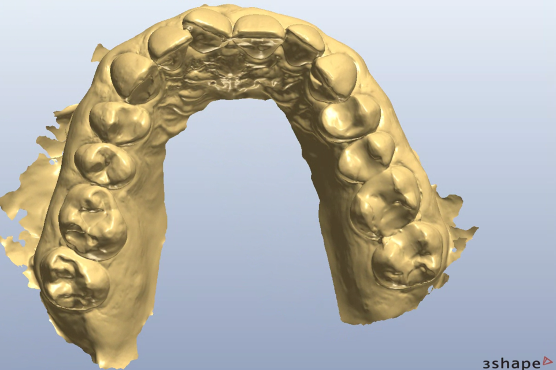

My workflows, which are followed from the Avant Garde training programme, always have the end point visualised and confirmed prior to commencement of treatment. Our treatment assessment, design, manufacture and implementation is also driven from an entirely digital foundation. The benefits of which I will touch on later.

Accuracy of preparation control is managed through several arms of the workflow:

- Diagnostic digital wax up; transferred to the mouth prior to tooth preparation to allow depth reduction burs to drive the amount of tooth prepared (Figure 5)

- Availability to use a 3D-printed removable transfer that shows the position of the final labial and incisal dimensions of the ceramic design. This can allow for direct measurements to be taken during the procedure with instruments like a Williams probe, confirming restorative space created

- A further fully digital clinical check communicated via the laboratory during the tooth preparation appointment. The laboratory have the diagnostic digital design, which can be accurately superimposed on top of a digital scan I can quickly create of the prepared teeth. I arrange ahead of the appointment some scheduled time for the laboratory to review this. They can give me sites where further reduction or modification is needed, to an accuracy of 0.1mm